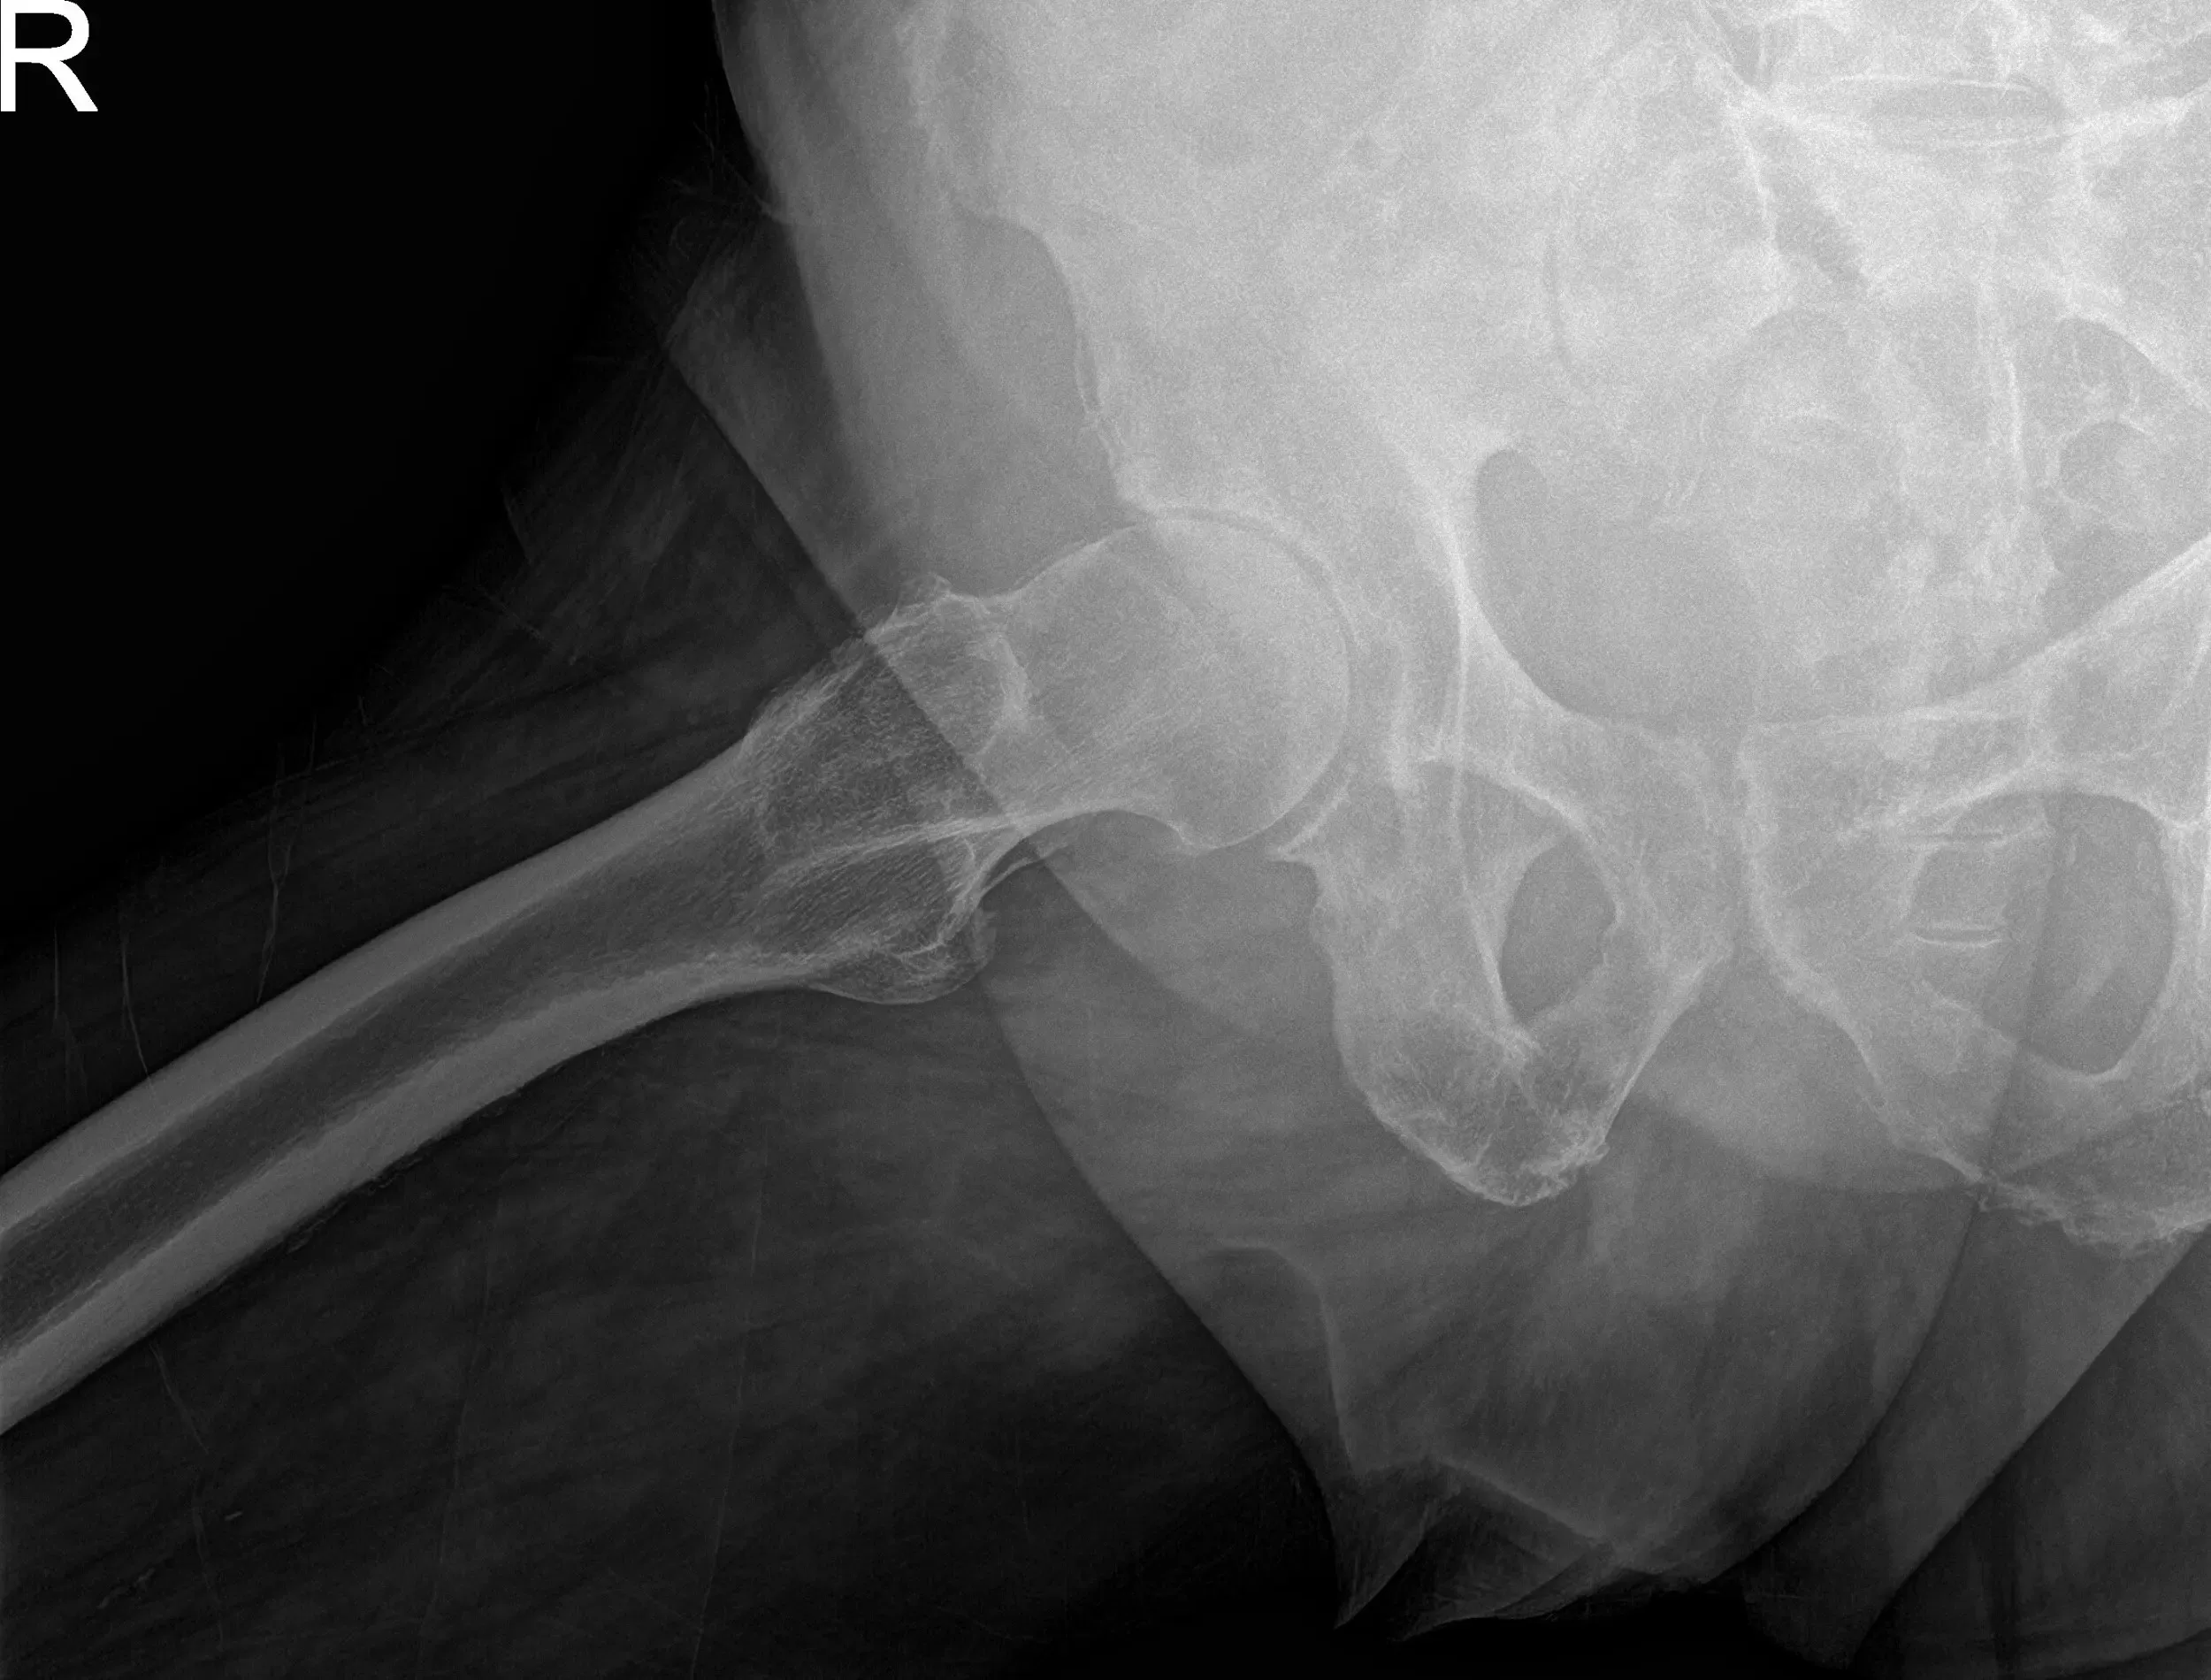

Radiographs of the pelvis revealed osteoarthritic changes in the right hip. Considering her comorbidities and lifestyle limiting hip pain, she was advised a total hip replacement surgery. She was made aware of the added risk of the surgery owing to atrial fibrillation and hypertension.